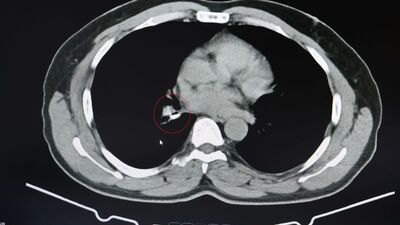

Şenyiğit, o maddenin zamanla akciğer yapısının özelliğini aldığını ve orada yabancı bir madde olarak kaldığına değinerek, "Hastamıza maalesef 2 yıldan beri astım tanısı konulmuş ve sürekli tedavi verilmiştir. Hasta bize geldiği zaman yapılan tomografide sağ akciğer ana bronşun distalinde şüpheli lezyon gördük. Uyguladığımız bronskokopide yabancı maddenin silikon olduğunu tespit ettik. Onu çıkardıktan sonra da hastada bir rahatlama meydana geldi" dedi.